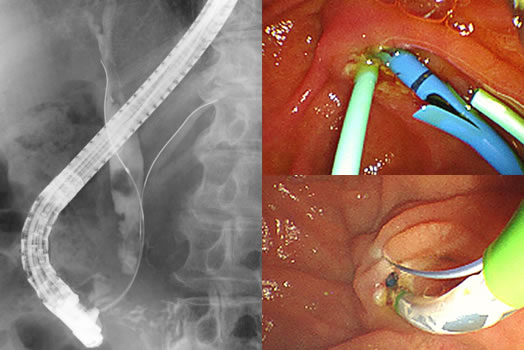

胆管・膵肝造影治療用内視鏡(ERCP)

口から飲む内視鏡を使って胆管・膵管を造影する検査をERCPといい、専用の内視鏡装置が必要です。ERCPは、総胆管結石、胆管がん、膵がんなどの診断と治療に有用です。当院では、緊急の治療が必要な急性胆管炎治療に熟達した医師の下で、24時間いつでもERCP下の胆道ドレナージを多数行っています。